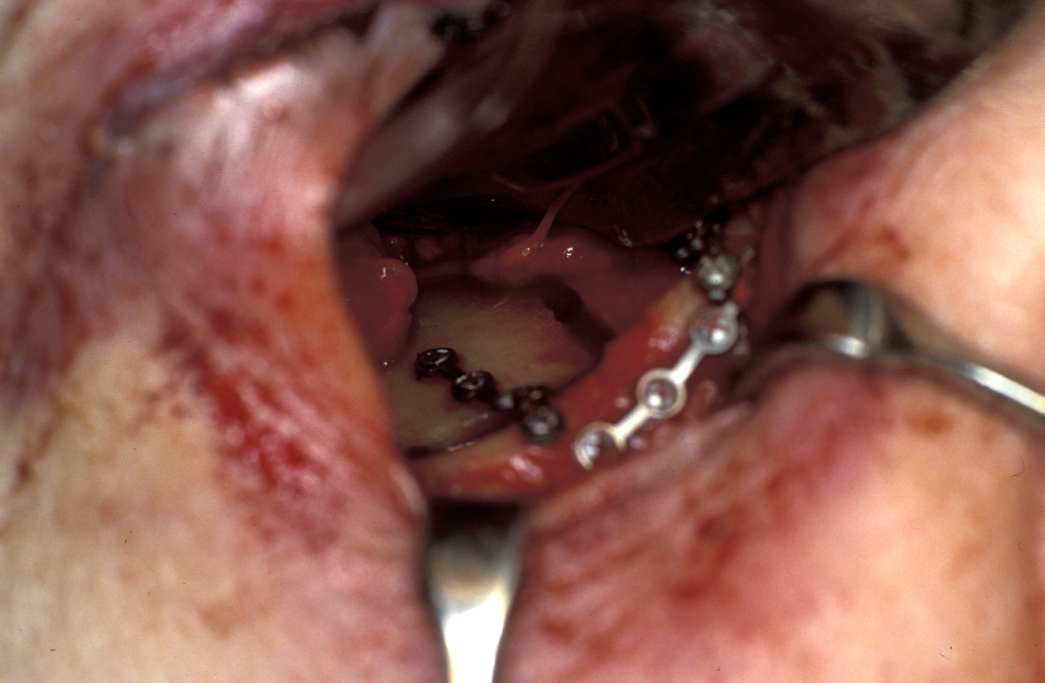

Definitive surgery usually involves open reduction and internal fixation (ORIF) under general anaesthesia, ideally using nasoendotracheal intubation. This allows the patient’s mouth to be closed and the teeth to be manipulated into their normal occlusion. This manipulation helps reduce the mandible into the prefracture bone position. Temporary intermaxillary fixation (IMF) is applied using a variety of techniques (trainee’s hand, eyelets, transalveolar screws (see Figure 1 and Figure 2), ‘rapid IMF’, arch bars). This helps to hold the fracture in its reduced position. Placing a bridle wire or tension band around the teeth can help reduce and temporarily fix the fracture.